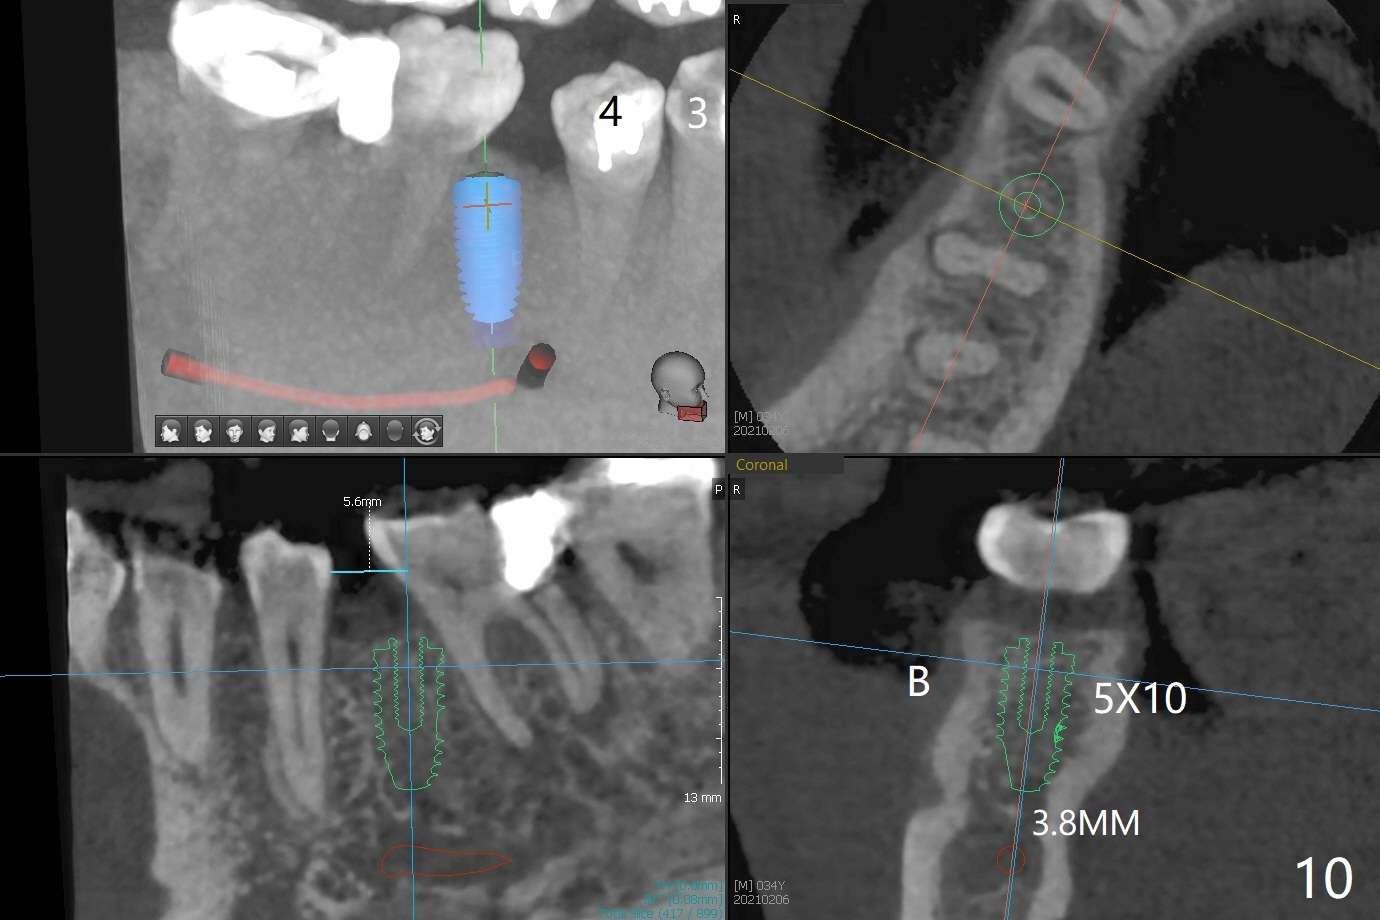

One year 4 months post banding (M) with 16x16 wires, UR3 is being distalized using UR7 as anchor (Fig.1), while the upper dental midline matches the facial one (Fig.2). The anterior overjet remains large (Fig.3). When UR3 is fully distalized, place posted wire to distalize U2-2 together. U2-2 distalization seems to be slow with one 16 mm closed coil spring each side (between 7 and post) 1 year 10 months post banding. Since the upper anterior PA shows mild root resorption at UR2 (Fig.4), a 14 mm closed coil spring is added each side (between 6 and post, Fig.5,6). LR6 has pain 2 years 2 months post banding (Fig.7). Debridement confirms non-salvageability; a 5x11.5 mm implant will be near the mesial root (Fig.8). Power chains for a month leads to closure of the gap between 3 and 4 (Fig.8-11). The space between 4 and 7 is 15 mm. A 12 mm 1st molar crown will be made, while the remaining 3 mm space will be closed by mesialization of 7 using 2 power posts mesial and distal to 6 and 7. Draw 2 tubes of blood. Make an incision to expose the mesial crest of 6.